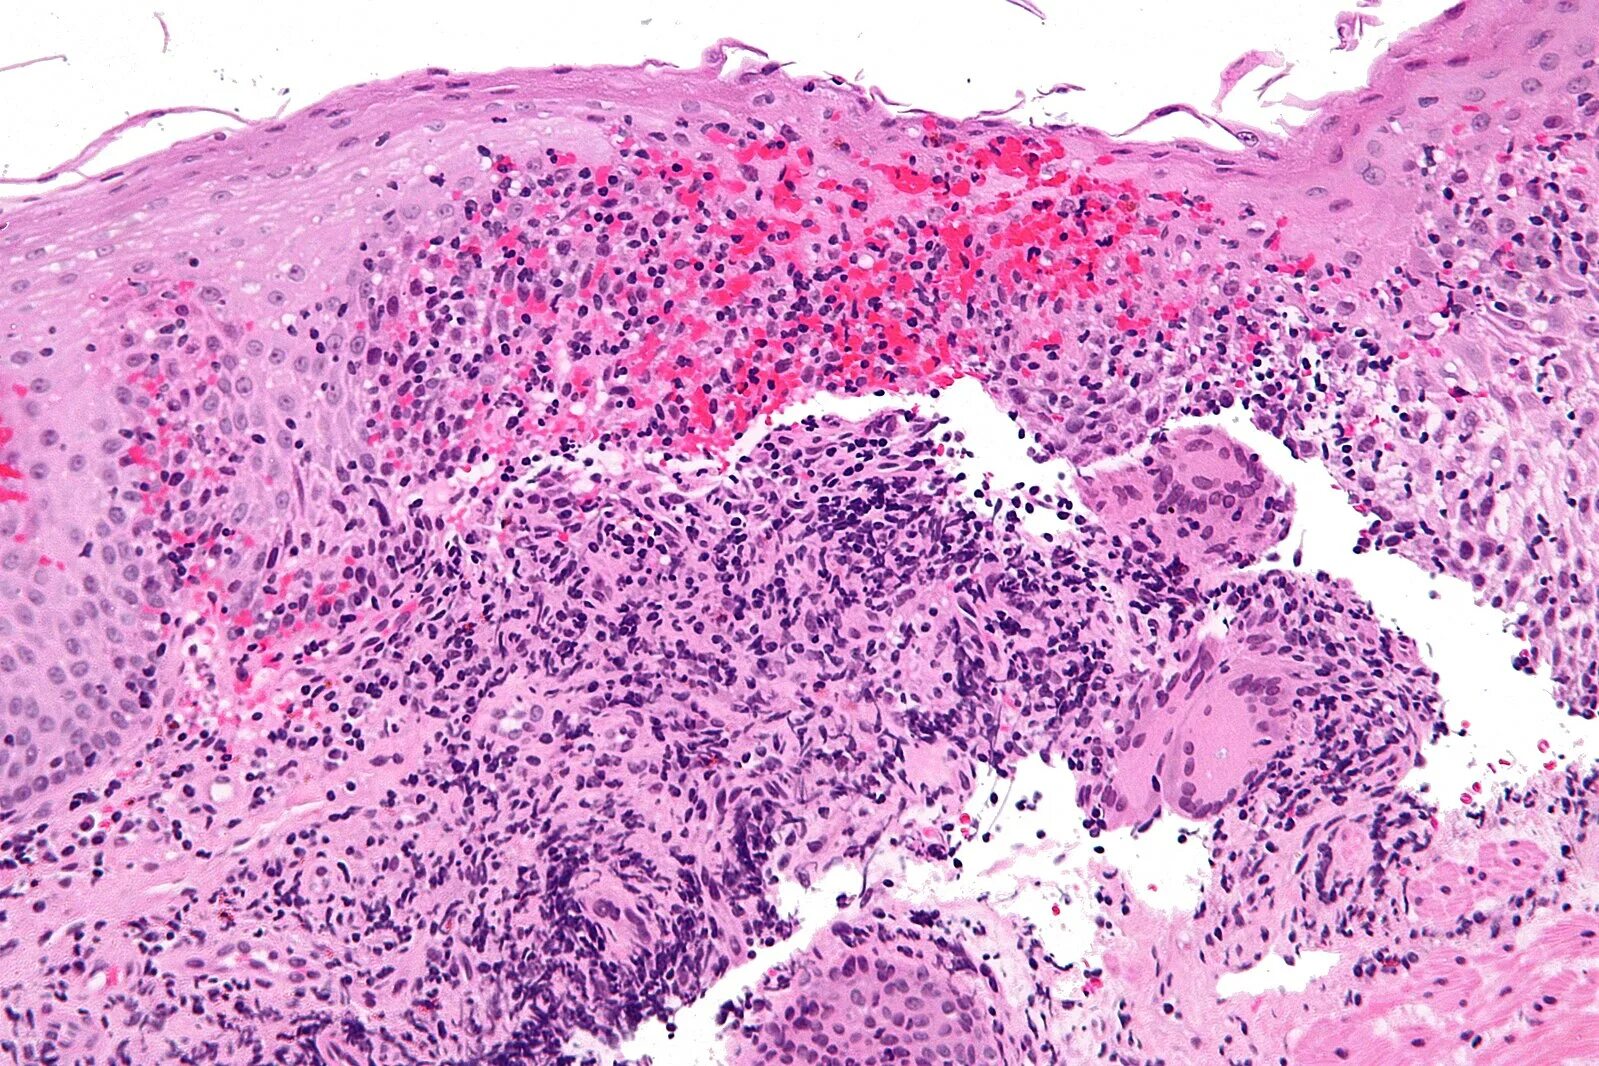

Гистологическая картина